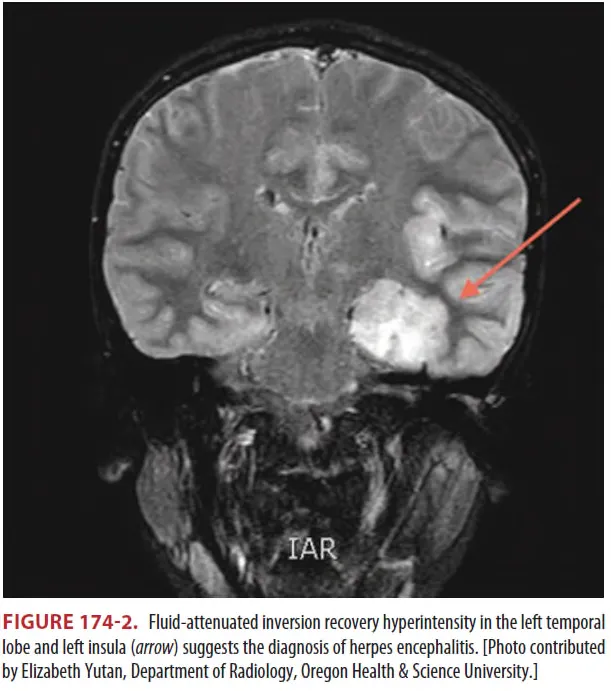

(2) HSV에서 Temporal or Inf. frontal lobe의 gray matter 침범

(1) MRI > CT